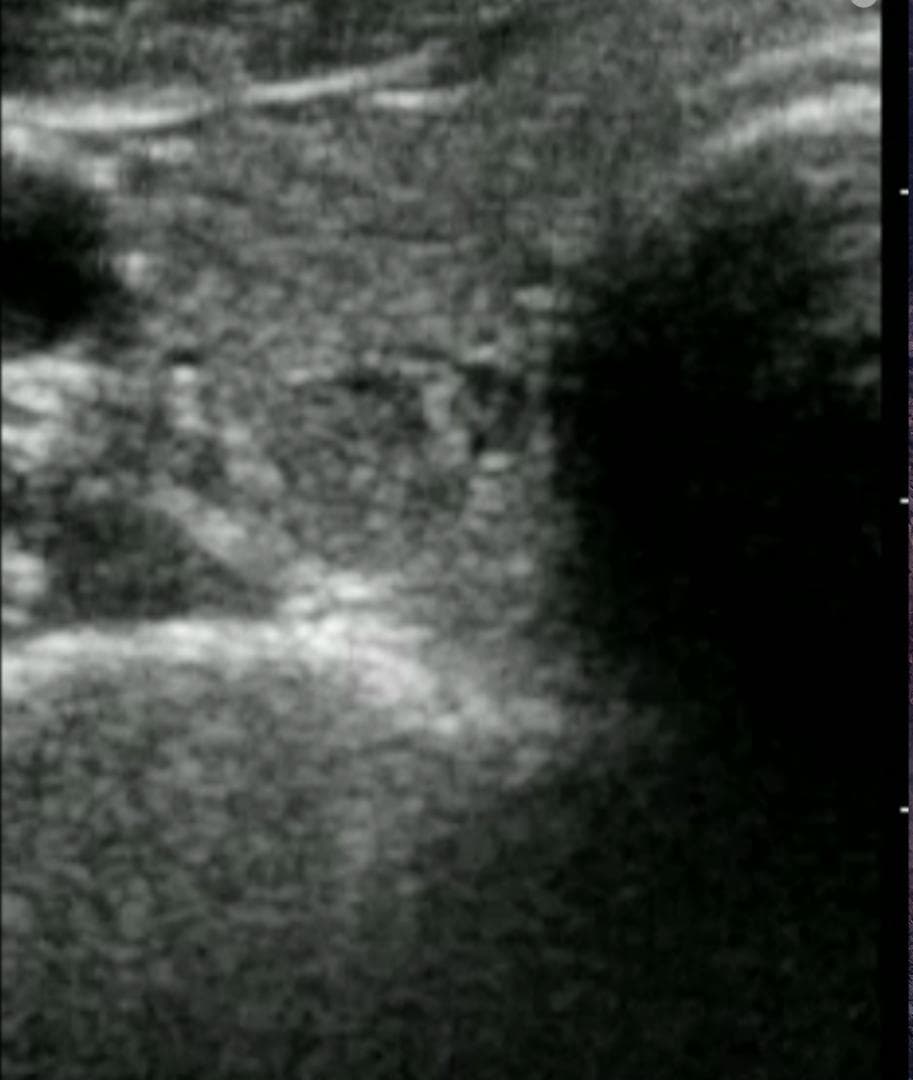

おわかりになる方のみの購入をお願いいたします実際に実施した写真をあげました正常肝臓、胆石症、頸動脈プラーク、同じく頸動脈プラーク、Mrの収縮期、同じくM弁の開放期とA弁の開放期、腹部大動脈瘤、正常の頸動脈、甲状腺右葉の結節、前立腺肥大画像の描出は条件によりますがご検討をお願いいたします経年変化、使用に伴うスレや傷などがあります機能に問題はありませんスキャンは心血管、腹部、体表に対応します外部接続端子のカバーが一部壊れていますが蓋は閉まりますバッテリーはフル充電されますが劣化はあると思います医療用モニタリング機器 Vscan Extend、GE- モデル名: Vscan Extend- ブランド: GE- 色: ホワイト- 機能: 医療用モニタリング機器ご覧いただきありがとうございます。鈴木 ALCARE Youcare-TDc 医療用テープ 25mm 6個。